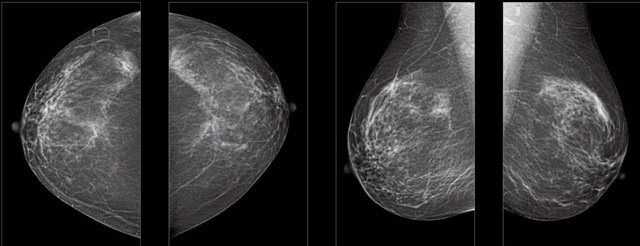

首先不同年齡階段的乳腺篩查頻次種類不一樣。青春期女性第二性征明顯發(fā)育開始,每個(gè)月進(jìn)行自我乳腺檢查。20-30歲的女性就不推薦進(jìn)行乳腺檢查,因?yàn)槟贻p女性的乳腺組織非常緊急。鉬靶X光線等檢查的射線不能辨別腫塊跟腺體。身體就白吸收了輻射,影響了身體健康。每個(gè)月自檢一次就是在洗澡時(shí)候,對(duì)著鏡子看看乳房外觀正常,皮膚潰爛、腫塊、顏色改變、再摸一下有沒小疙瘩。乳腺高危人群,特別是有乳腺CA遺傳傾向的女性,乳腺導(dǎo)管跟小葉不典型增生,原位癌。30歲前有乳房放療的女性。乳腺癌篩查可以把年齡提前到40歲前。40到70歲的女性可以在適合的機(jī)會(huì)篩查。

采用影像檢查技術(shù)來發(fā)現(xiàn)疑似特定病檢查跟人群的普查。一到兩年進(jìn)行一次X光線的乳腺檢查。記過是C或者D型,可以加上B超協(xié)同。還可以一年一次核磁共振MRI檢查。70歲以上的女性認(rèn)為絕經(jīng)的女性是比較安全的。實(shí)際上也有乳腺癌的風(fēng)險(xiǎn)。65歲以上風(fēng)險(xiǎn)也很大。也是需要進(jìn)行機(jī)會(huì)性篩查。